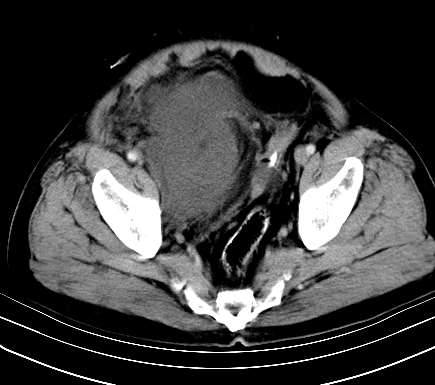

增强扫描

静脉期

【ct表现】

1、肿块巨大,往往位于腹膜后,长大后才引起症状而就诊;那么位于腹膜后的肿瘤80%为恶性肿瘤。

2、实性肿瘤,增强扫描轻度不均强化,实性肿瘤一般不是好东西。

3、肿瘤边缘似见少许脂肪样密度。

4、腹膜后未见肿大淋巴结,但肿瘤于临近的肠管及组织接触紧密。

【诊断】

腹部占位,考虑位于腹膜后的恶性肿瘤,脂肪肉瘤(实体型)可能性大。

【分析】

1、腹膜后的肿瘤少见,但种类繁多,包括脂肪肉瘤、纤维组织细胞肉瘤、纤维肉瘤、平滑肌肉瘤、恶性畸胎瘤、神经肉瘤、神经母细胞瘤、血管肉瘤及横纹肌肉瘤等,其中脂肪肉瘤为较常见的一种肿瘤。

2、增强扫描强化不明显,除脂肪肉瘤以外,一般肿瘤强化中度以上。脂肪肉瘤可不强化或轻度强化。

术后病理结果:腹膜后脂肪肉瘤。